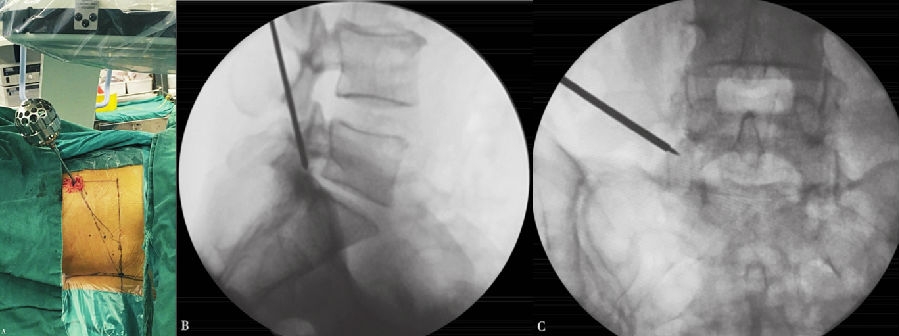

以L5~S1为例,根据髂嵴的高低,针尾向头侧倾斜约 40°~60°,外展角约 30°~50°,定位针在正位X线透视下刚好位于后背正中的棘突连线上,侧位X线透视下则紧贴上关节突腹侧,下缘位于下位椎体的后上缘。(图6)

6. 置入定位器

在上关节突上打孔,退出扩张器,再磨除部分关节突关节,逐级扩大椎间孔。(图9~图13)

图5-图9 A:使用利多卡因进行局部分层麻醉(皮肤、皮下组织、筋膜、关节突周围);B:穿刺针X线片侧位投影图;C:穿刺到位后交换导丝;D:导丝引导下通过导杆、三级套管扩张肌肉及软组织;E:导丝引导下交换Tom针,定位上关节突

图10 Tom针定位上关节突

A. Tom 针定位上关节突;B.Tom 针X 线片侧位投影图;C.Tom 针X线片前后位投影图

图11-图13 6mm扩孔骨钻扩孔过程中;6mm扩孔骨钻侧位X线片投影图;8mm扩孔骨钻前后位X线片投影图